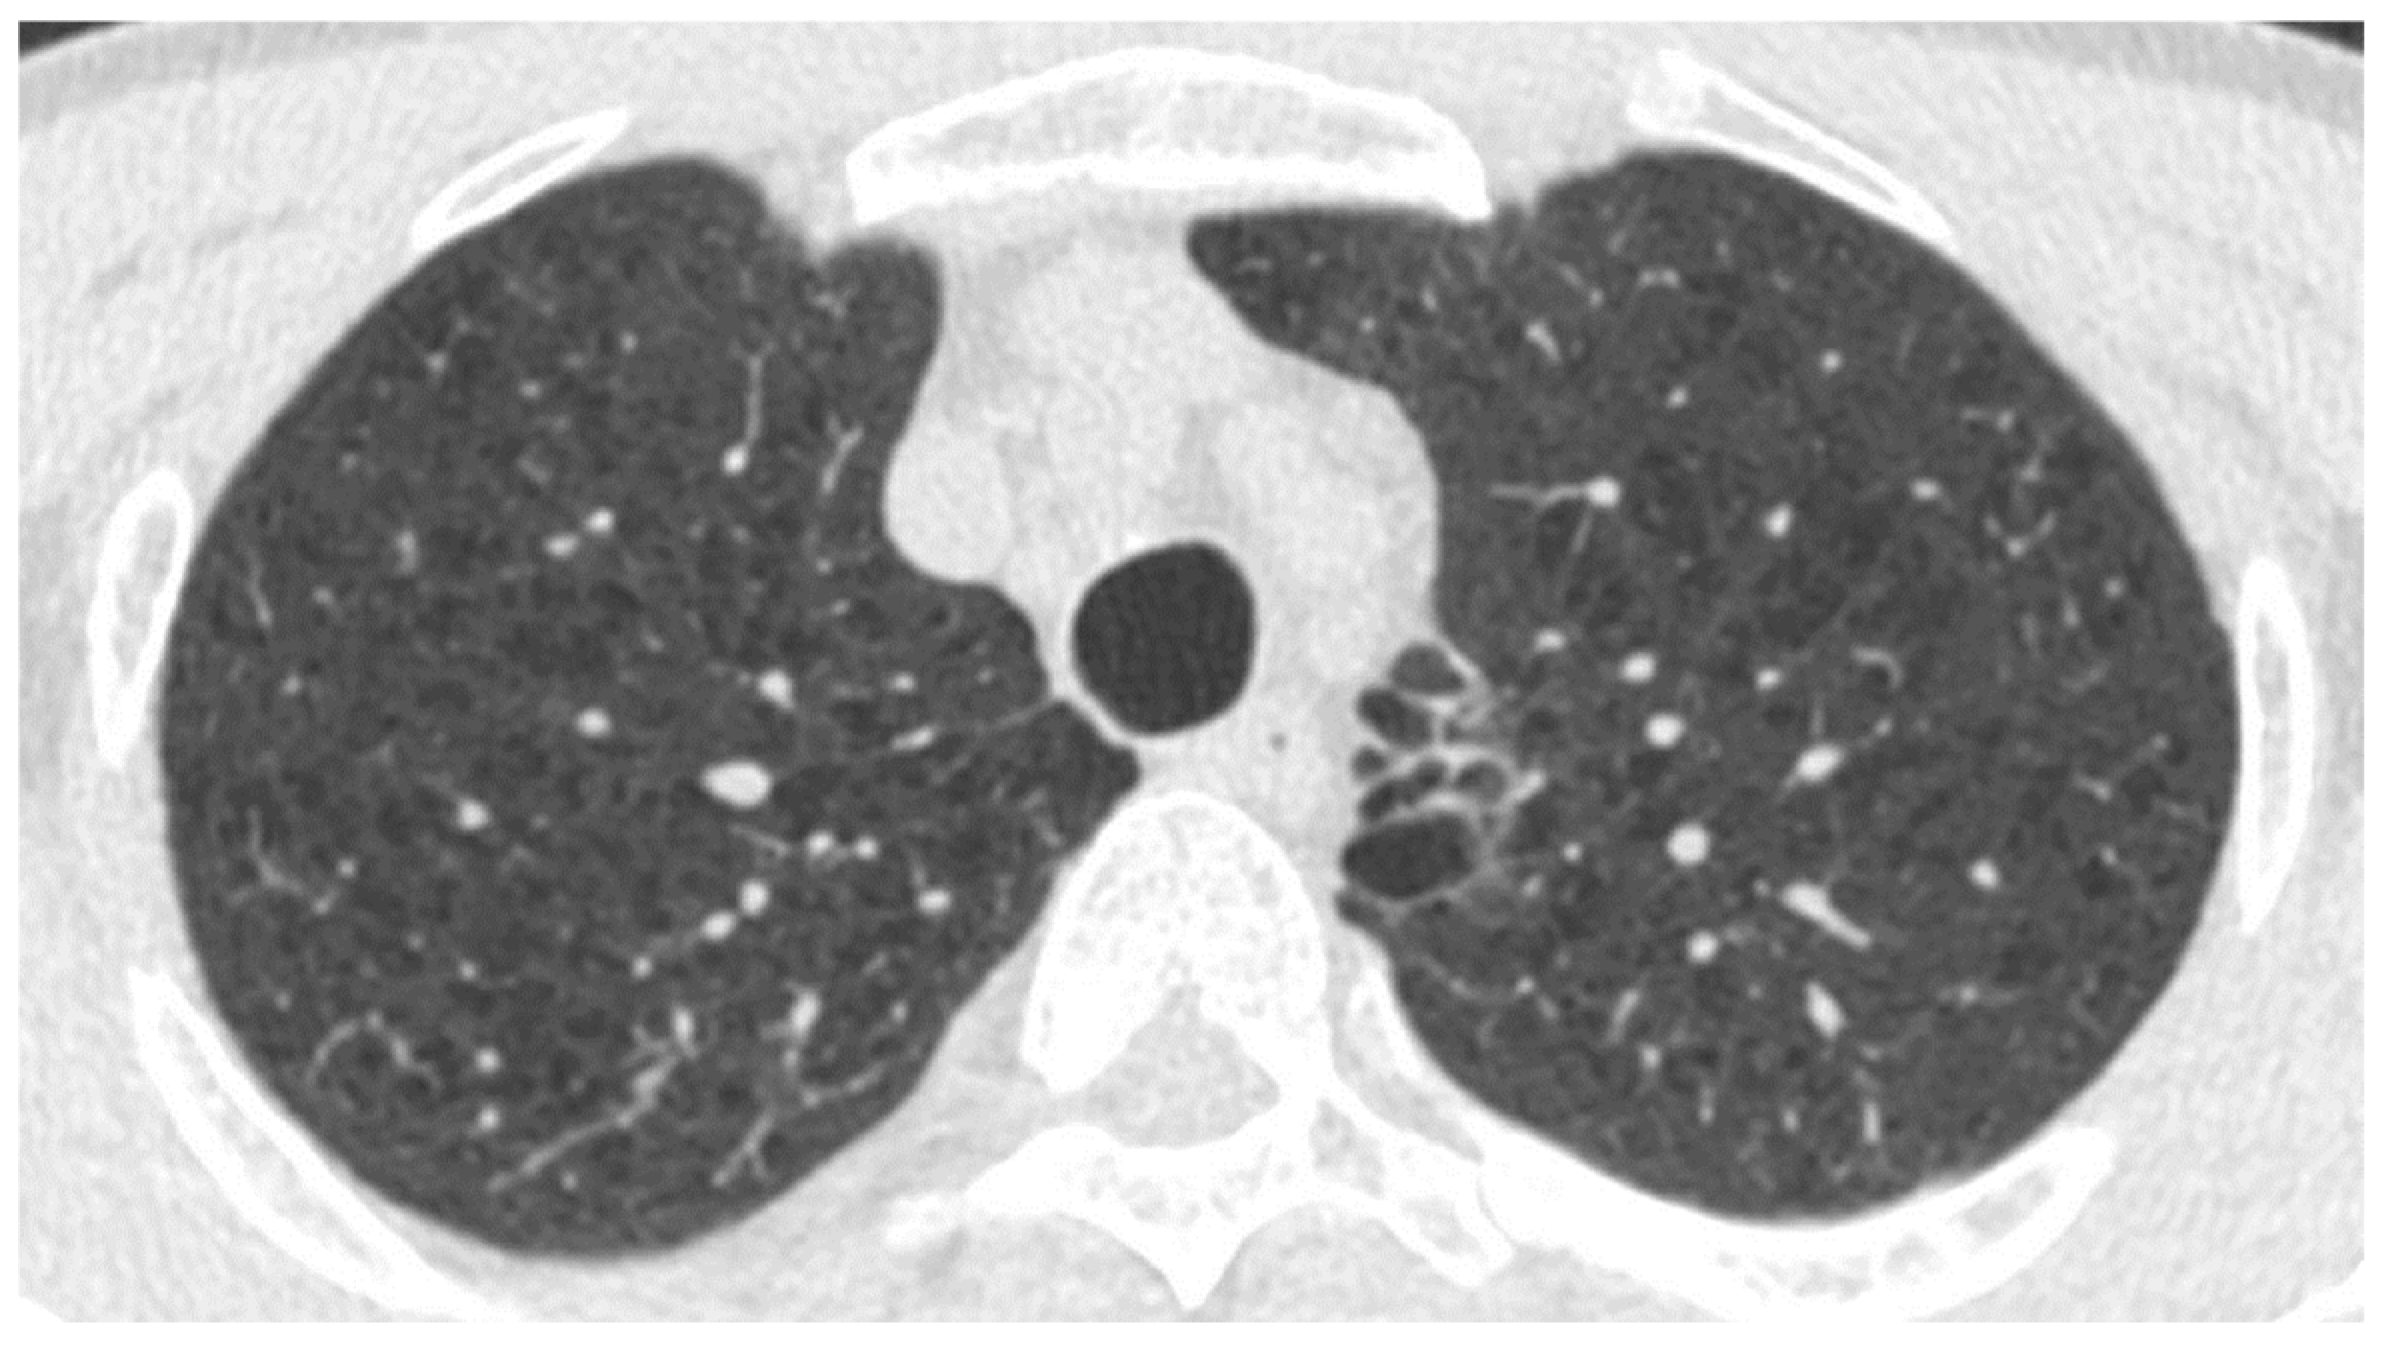

3.2. Interstitial Lung Diseases (ILDs)